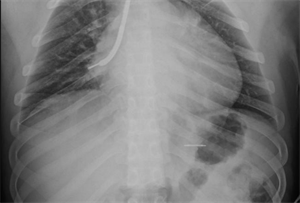

白主任还邀请消化内科副主任吴斌、胸外科许涛医生一同到场,齐心协力保障患儿。然而,白主任用支气管镜反复多次查找,却始终没有发现异物,同时使用小探头超声内镜扫描,也一无所获。考虑有移位可能,白主任果断建议床旁摄片,进行气管镜下定位。时间紧迫,影像科技师汪津立刻带着机器来到气管镜室。经过摄片,发现金属异物显影在了胃泡里!